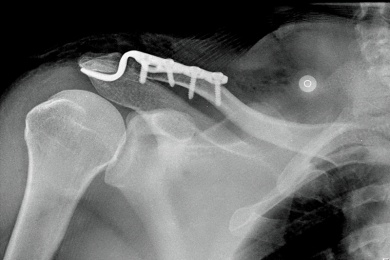

In manchen Fällen ist aber eine Operation erforderlich, zum Beispiel wenn eine Verschiebung des Bruches ohne Einrichtung droht oder es sich um einen offenen Bruch handelt. Bei einer Operation werden die Knochenteile, die sich bei der Fraktur verschoben haben, wieder in die richtige Position gebracht, was mit manuellem Druck oder Zug bewerkstelligt wird.

Dann werden die Knochen mit Hilfe von Metallplatten, Schrauben, Drähten oder Nägeln bis zur erfolgreichen Heilung des Knochens fixiert.

Schlüsselbeinbruch - Ursachen, Symptome und Behandlung